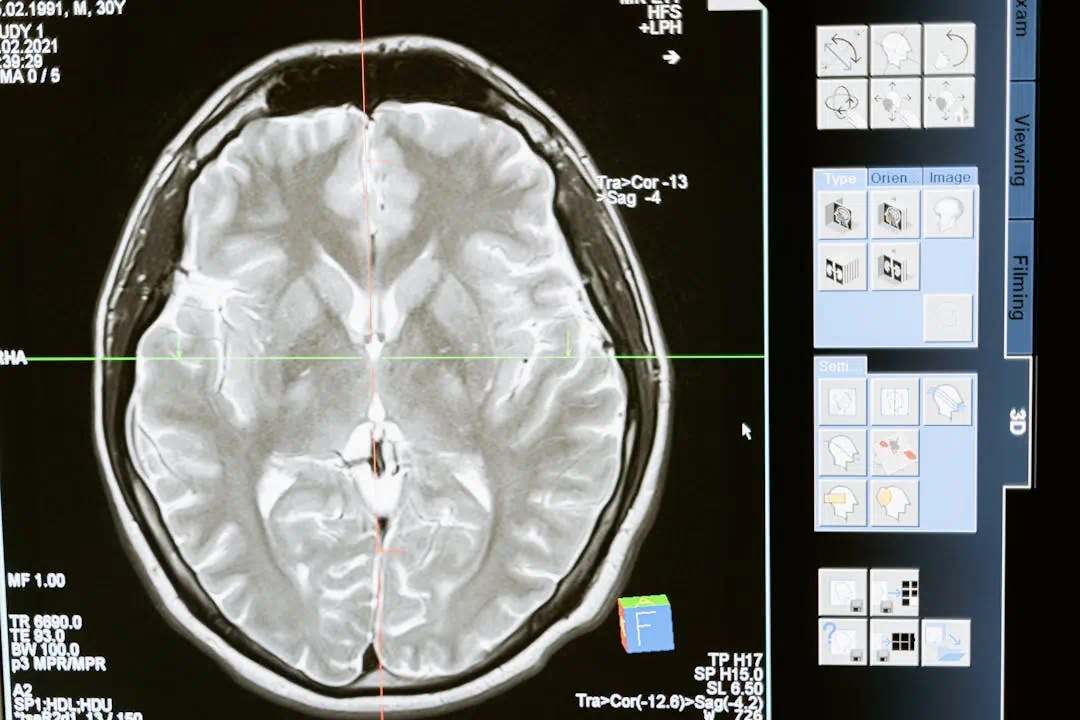

뇌경색 관련사진으로 두통의 모습을 표현4뇌경색 관련사진으로 두통의 모습을 표현5뇌 MRI 사진의 모습

뇌경색 초기증상 놓치면 위험합니다